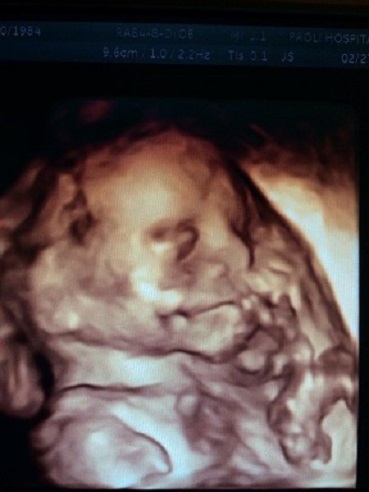

We kind of had a gap in pictures between weeks 10 and 20. Mostly because we didn’t want to jinx ourselves and create the entire string of photos that we wouldn’t want to look at if something had happened. So we took a break from that. Kelly was feeling much better and showing. No more morning sickness, she started to get some of her energy back and our 20 week Ultrasound revealed 10 little fingers, 10 little toes, 2 arms, 2 legs, 2 little feet, a whole bunch of other baby parts, a smirking face, and we are assuming a penis or the absence of a penis. We aren’t finding out the sex so we kept that a surprise. No sign of Down Syndrome or any type of birth defect, but Kelly still needed to complete the blood test portion of the Sequential Screening to rule out Down Syndrome and other issues, routine stuff really. All eventually came back normal and we were on our way. Here is the Kelly Belly (I’m calling it that from now on) at 20 weeks: